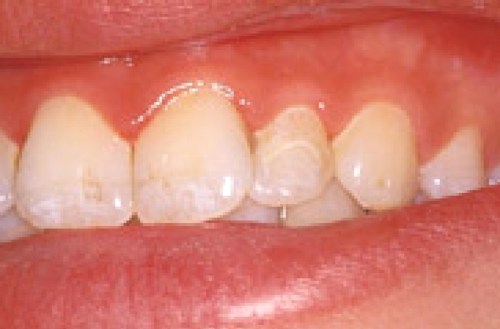

Nedenfor ses en billedserie, der illustrere forløbet.

- Hjørnetanden på plads i tandrækken.